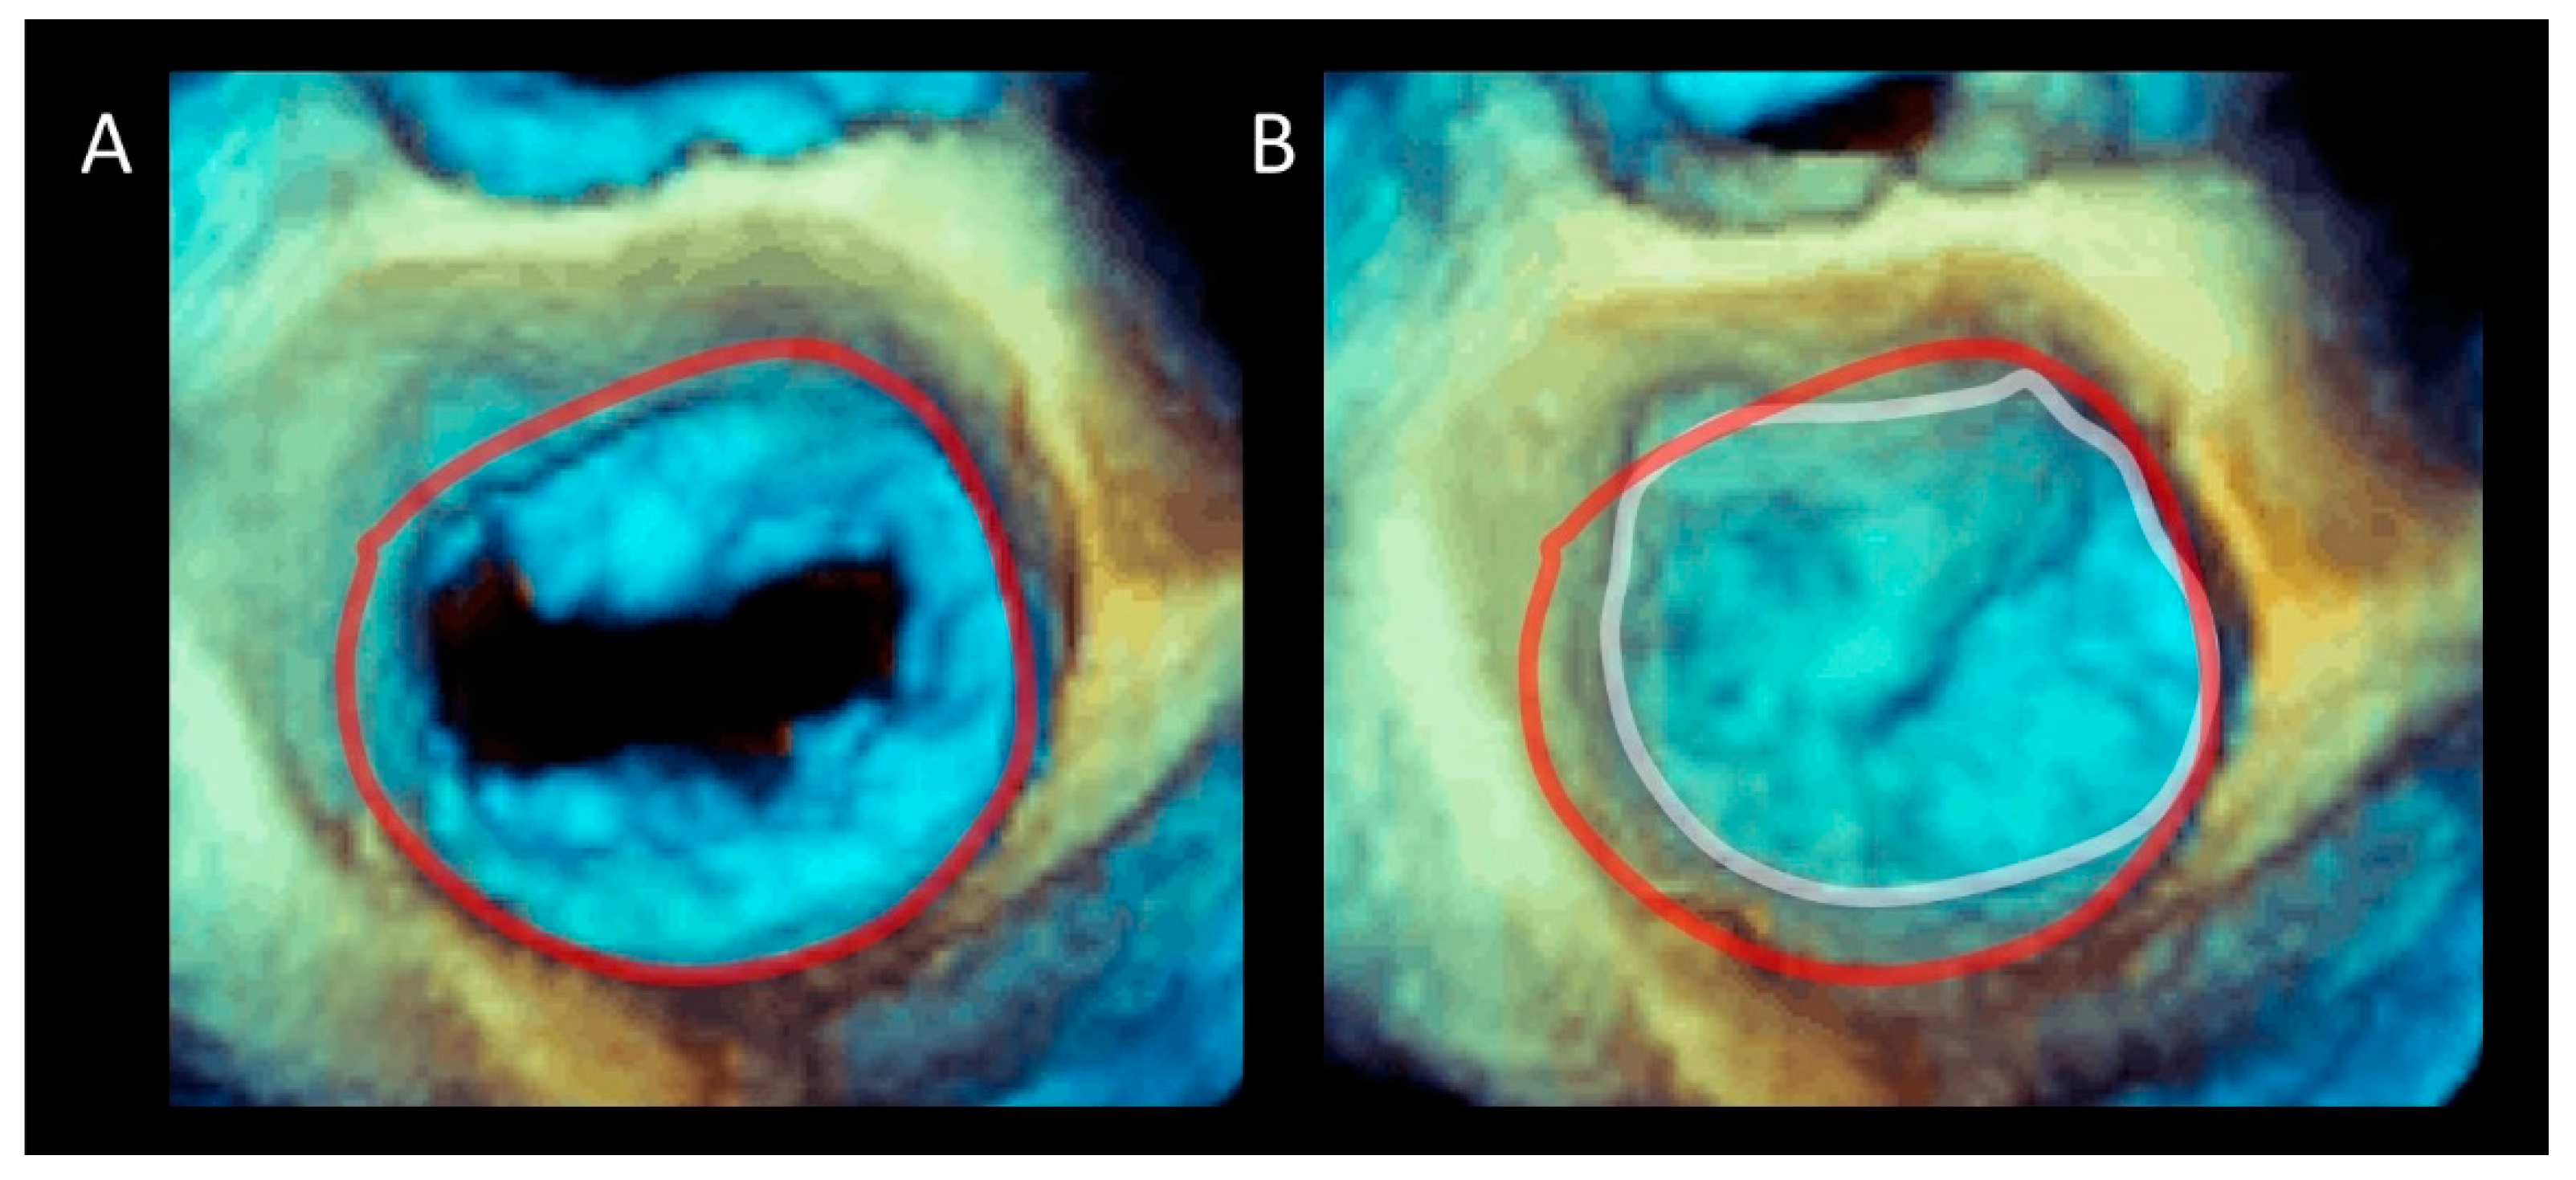

Figure 3.

Three-dimensional TEE image of the mitral valve (MV) from an overhead perspective in (A) diastole and (B) systole. The sphincteric action of the annulus is marked with a red (diastolic) and white (systolic) circumference.